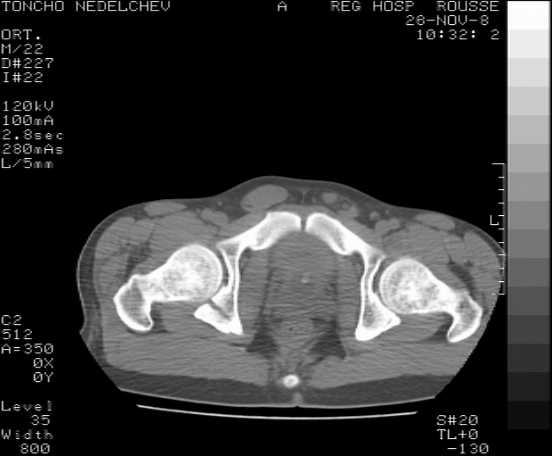

Here are some more axial images. What is your opinion as for the timing of the operative treatment?